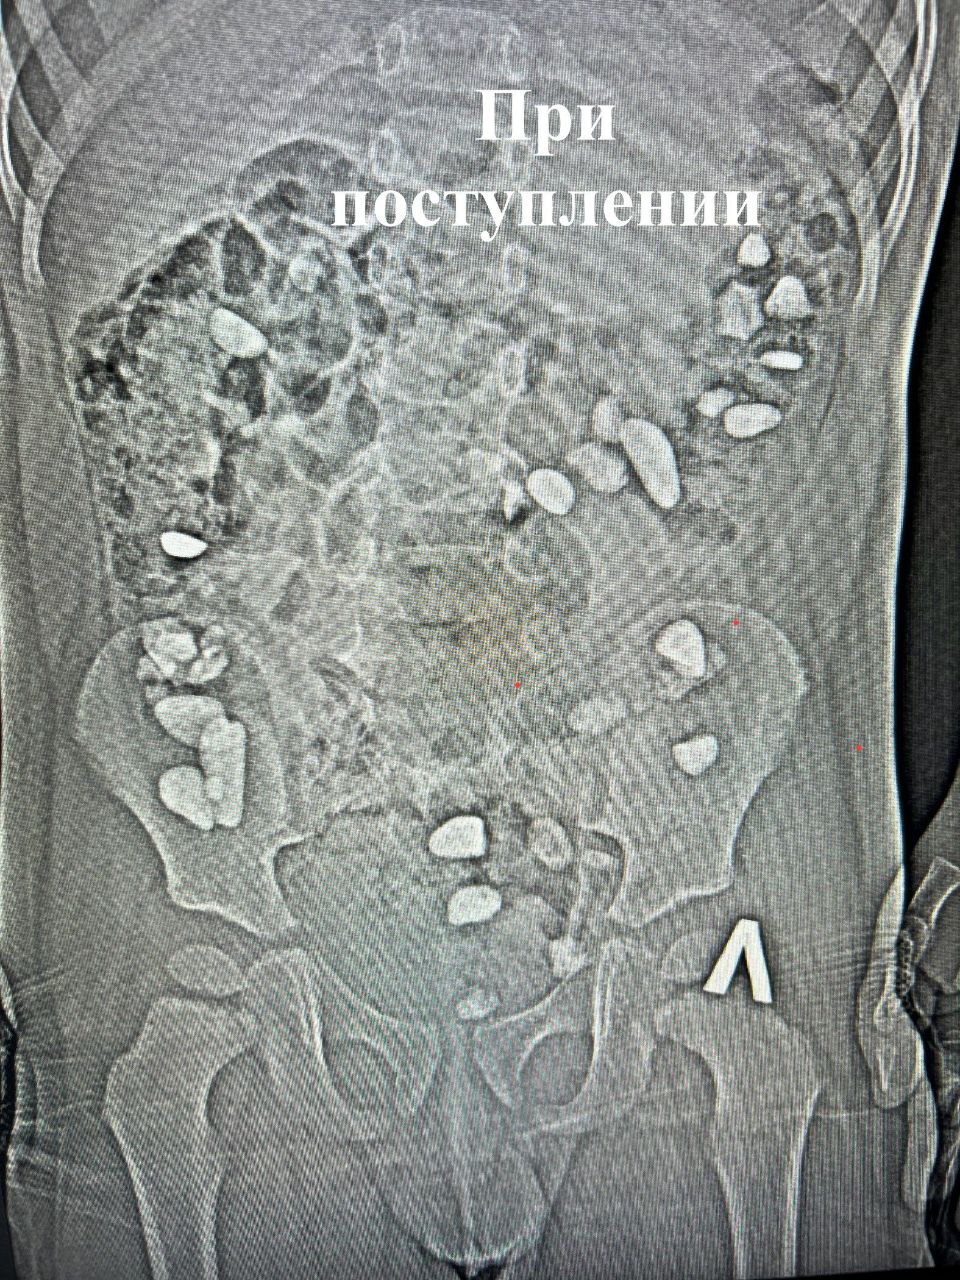

В больницу малыш поступил с жалобами на боли и вздутие живота. Рентген показал, что мальчик проглотил более 25 камней. Как это произошло — родители не знают.